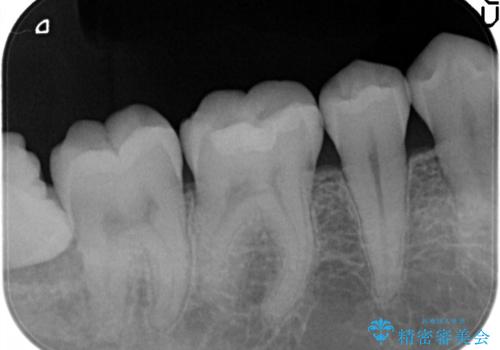

メタルフリーの治療 セラミックインレー

- メタルインレーによる審美障害を主訴に来院されました。

セラミックインレーに治療を行っております。

e-max プレスインレーにて修復治療を行っているため適合性及び審美性の高い治療を行うことができます